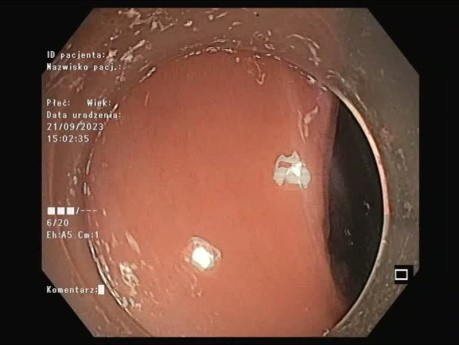

Płaska zmiana LST-G w odbytnicy

Wideo ukazuje pEMR zmiany w odbytnicy. Płaska zmiana LST-G (Polipowata zmiana typu LST-G (ang. laterally spreading tumor, granular)) w odbytnicy.